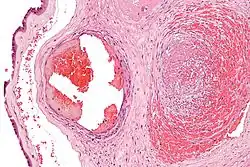

| Intermediate magnification micrograph of the placental disc showing a thrombosed fetal vein, as may be seen in fetal thrombotic vasculopathy. H&E stain. | |

It can be diagnosed by histomorphologic examination of the placenta and is characterized by fetal vessel thrombosis and clustered fibrotic chorionic villi without blood vessels.